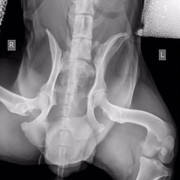

Нас 6-ро, и все они замечательные ребята с большим сердцем. Эта ситуация личная для меня, и я всеми силами хочу сделать добро, вылечить животное, которое я собственноручно вытягивала с проезжей части, которого гладила, пока ему ставили капельницу и измеряли давление врачи круглосуточной ветклиники. Спокойный умный пёс, который оказался на улице по вине человека. Он не щенок, он в самом расцвете, думаю, но такой добрый, отзывчивый и спокойный, и борющийся за жизнь. У собакена перелом таза, сильные ссадины, осколки таза навредили внутренним органам и нужна операция, последующее дорогостоящее и долгое восстановление. Также есть вопросы по дерматологии, пёсель уличный - завтра врачи возьмут соскоб, чтобы попытаться восстановить волосяной покров животного.

Собаке сделали операцию, но не на тазу (таз вправили ректально), а на передней лапе, которая оказалась сломана, но в виду того, что собака была лежачей и болезненно реагировала на перемещения по клинике, про перелом выяснилось позже. Поставили спицы.

У него есть чувствительность задних лап, поэтому проводимость есть. В туалет пошел сам. Врачи говорят операция на тазу не нужна.

Цитата Саша (  )  говорят операция на тазу не нужна.У него перелом таза, что гораздо серьезнее его сломанной и прооперированной лапы. У него же таз перекошен и лучше вряд ли при постоянном движении будет. Снимки таза и пса самого осматривал опытный травматолог?

Ну дело, конечно, хозяйское, или кураторское точнее, но я бы поинтересовалась, какой прогноз лечащий врач даёт при консервативном лечении (вернее нелечении) сломанного таза и когда планируется контроль сращения. Потому что при постоянной подвижности костей в месте перелома таза есть угроза того, что пёс станет инвалидом. При правильном лечении и фиксации - выздоровеет полностью. Здесь ведь на форуме небезразличные люди собрались и советы дают из своего волонтерского опыта (вам советовали везти пса к проверенным опытом травматологам, пч все ветеринары - специалисты широкого профиля, и лишь единицы являются узкими и грамотными специалистами в определённой области, в травматологии в частности, чему учатся годами). Вашему подопечному все желают только скорейшего выздоровления, поэтому и пишут здесь

меня зовут Алена и я одна из очевидцев и посетителей Собакена. спасибо большое, за ваше внимание к нашей истории и за желание помочь!!на данный момент его снимки смотрели в САСе, а также лечащий врач моего кота (Мурыченков Евгений - отличный врач, много раз возвращал моего Зефира с того света). оба врача сейчас подтвердили что таз оперировать нет необходимости, как нам объяснили процесс заживления будет в обоих случаях аналогичный (шуруп Собакен может вырвать случайно, при постановке шурупа этого возможно повредить нервы). чувствительность ног у него в порядке. соскоб на клеща делали, но его не нашли, возможно это нарушение функции надпочечников. но нам порекомендовали полечиться от клеща после того как у него восстановится печень (сейчас множественные ушибы внутренних органов)